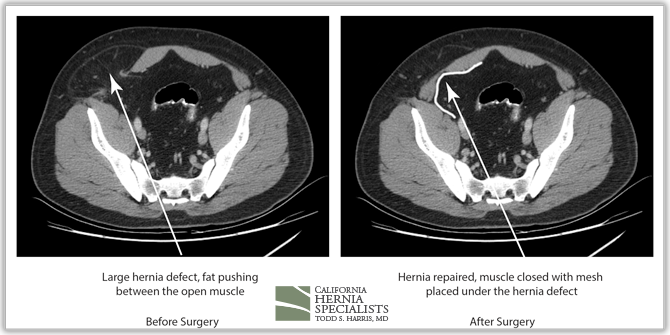

Because this patient had failed two prior surgeries, we performed a complex open hernia repair on him. This repair included a technique called ‘component separation’, where the oblique muscles on the sides of the abdomen, are partially released, or cut, to allow the rectus muscles to be pulled back together in the middle of the abdomen.

Since the abdominal muscles were weakened, we placed a sheet of biologic mesh under the muscle in the middle at the area of the hernia hole, closed the muscle over this mesh, then placed another mesh on top of the muscles which were closed. This provided him with three layers of repair.

The CAT scan image below compares the patient before surgery, and then after surgery when the muscle has been pulled back together and the hernia has been repaired.